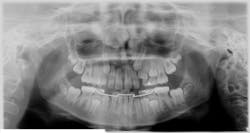

In this clinical case, a patient with impacted maxillary canines was re-evaluated using an i-CAT FLX from KaVo Imaging (manufactured by Imaging Sciences International LLC) The 3D views allowed for better determination of the clinical status of the patient by bringing more clarity to the labiolingual relationships of the impactions and the identification of any associated complications, such as root resorption in adjacent incisors.